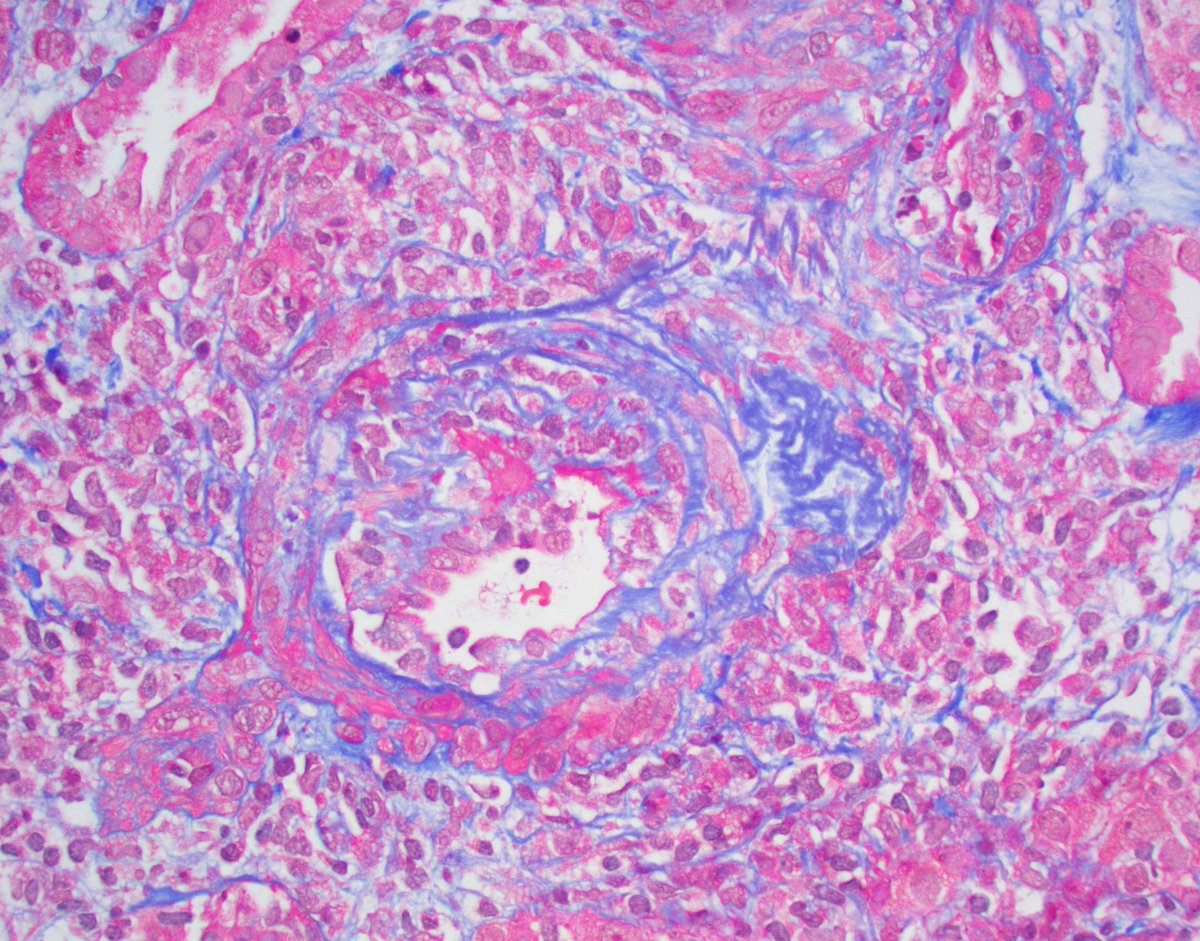

Mini case-series of crystal-storing histiocytosis (CSH) affecting predominantly glomerular loops with detailed literature review of renal CSH, images of one of the cases are depicted below, authors.elsevier.com/c/1Zh4S3uV~y8B…